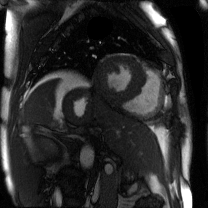

Supervised Deep-Learning (DL)-based reconstruction algorithms have shown state-of-the-art results for highly-undersampled dynamic Magnetic Resonance Imaging (MRI) reconstruction. However, the requirement of excessive high-quality ground-truth data hinders their applications due to the generalization problem. Recently, Implicit Neural Representation (INR) has appeared as a powerful DL-based tool for solving the inverse problem by characterizing the attributes of a signal as a continuous function of corresponding coordinates in an unsupervised manner. In this work, we proposed an INR-based method to improve dynamic MRI reconstruction from highly undersampled k-space data, which only takes spatiotemporal coordinates as inputs. Specifically, the proposed INR represents the dynamic MRI images as an implicit function and encodes them into neural networks. The weights of the network are learned from sparsely-acquired (k, t)-space data itself only, without external training datasets or prior images. Benefiting from the strong implicit continuity regularization of INR together with explicit regularization for low-rankness and sparsity, our proposed method outperforms the compared scan-specific methods at various acceleration factors. E.g., experiments on retrospective cardiac cine datasets show an improvement of 5.5 ~ 7.1 dB in PSNR for extremely high accelerations (up to 41.6-fold). The high-quality and inner continuity of the images provided by INR has great potential to further improve the spatiotemporal resolution of dynamic MRI, without the need of any training data.